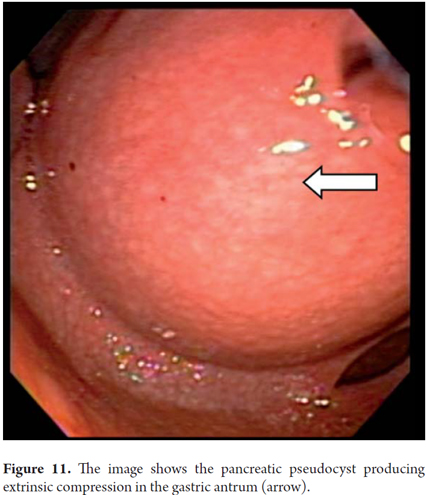

If the pseudocyst bulges or protrudes into the gastric cavity or duodenum, it is usually considered that it can be drained without the guidance of ultrasound endoscopy which is reserved only for cases where there is no compression of the lumen. Nevertheless, our group considers that all pancreatic pseudocysts should be drained with prior EU since there is always the risk of having a vessel in the gastric wall that separates the collection of fluid. These lesions are very dynamic and are very likely to break in the course of their evolution. This can be detected by EU. This was the case when a 9 year old girl was referred to us for drainage of a pseudocyst. An MRI (Figure 11) that had been taken eight days before indicted the pseudocyst. Nevertheless, when we evaluated the patient for drainage, we observed that it had broken into the cavity resulting in pancreatic ascites. In addition, it should be noted that for drainage of small pancreatic pseudocysts (5 cm), a #19 needle guided by EU is often sufficient for complete aspiration. If we choose the endoscopic route, transduodenal drainage is preferable to gastric drainage if both are feasible. Also, insertion of a dual 10 F pigtail prosthesis has fewer complications than insertion of a straight, and is therefore preferable. This is also the recommendation of the American Society for Gastrointestinal Endoscopy (ASGE). If it is possible, you should place two prostheses because the use of a double prosthesis has fewer recurrences than the use of only one. A follow up CT scan should be done 2 months after the procedure. If there is no evidence of collected fluid, the pseudocyst should be removed endoscopically. In our series, most patients' pseudocysts resolved within 2 or 3 months and only one patient required two prostheses.

We will describe the technique we have been using in our service for about5 years. The patient is sedated by an anesthesiologist and is placed in left lateral position. Then we introduce the endoscope. Next, we find the pseudocyst (Figure 11) and the wall that separates it from the gastric lumen. We evaluate it by measuring its thickness and using a Doppler signal to rule out the presence of vessels (Figure 12). Once the site chosen has been located, we mark the area with biopsy forceps (or ink), then we remove the echoendoscope and replace it with a duodenoscope which we believe provides better angulation for drainage. After introducing a guided papillotome needle with coagulation current set at 30V, the wall is perforated (Figure 13). Once entry to the pancreatic pseudocyst has been achieved, the guide wire should be advanced guided by fluoroscopy (this is not strictly necessary: we have drained some cases in the endoscopy room). The coagulation hole can now be extended to 2 or 3 mm in diameter using the same papillotome for cutting (Figure 14). This will allow passage of the prosthesis (this step can be done with a biliary dilatation balloon, but it is more expensive). The papillotome is then removed and the prosthesis is advanced (Figure 15). Then the orifice is cannulated again, and - using the same method - we place the other prosthesis. Double pigtail 10 Fr type prostheses should be placed. For 5days following the procedure, 1.5 grams of ampicillin/sulbactam should be administered orally every 6 hours, and 1 tablet of fluconazole should be administered daily (8, 9). Because of the high rates of recurrence, prostheses should remain in situ for 8 weeks. At the point another CT scan should be performed. If there are no residual lesions, the prostheses should be removed (4).